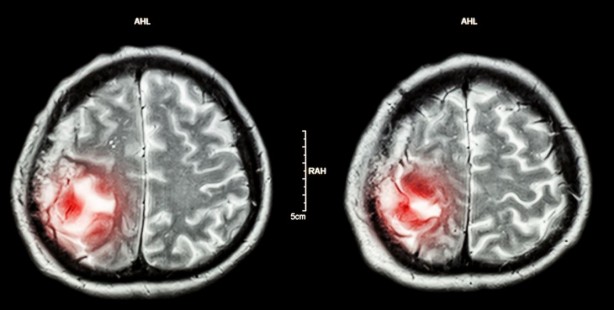

Sonuçlar ise oldukça şaşırtıcı. ChatGPT yüzde 73'lük bir puan alarak nöroradyologların (yüzde 72) ve genel radyologların (yüzde 68) doğruluk oranını geride bıraktı.

Nöroradyologların raporlarını yorumlarken, AI modeli yüzde 80'lik bir doğruluk oranına ulaştı.

Ancak genel radyologların raporlarına gelince bu sayı yüzde 60'a kadar düştü.

Yani raporun arkasındaki radyolog türü, ChatGPT'nin teşhislerinin ne kadar kesin olacağını gerçekten etkileyebilir gibi görünüyor.